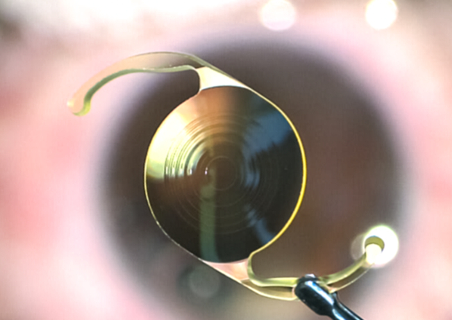

晶体植入icl加不加散光区别大吗?晶体植入以及人工晶体植入是近视矫正手术当中比较常见的一种方法了,与激光手术不同的是能够修改角膜形态,其中晶体植入icl以及人工晶体植入,主要是通过植入人工体来矫正视力,所以并不会对角膜产生影响,比较适合存在严重近视以及角膜薄的人群。很多人不仅近视也有散光,那么晶体植入icl加不加散光区别大吗?这篇文章就为大家详细解说这些问题。

(1)矫正视力问题:带有散光的晶体植入,能够同时矫正近视与散光,视力会更加清晰,不带有散光的晶体植入主要是用来矫正近视的,但是矫正结果会有一定程度的限制。

(2)适用人群:散光度数高的顾客比较适合选择带散光晶体植入,如果散光度数较低并且没有散光的顾客,那么就不用带散光的晶体植入。

(3)视觉作用:带有散光的晶体植入可以较好改良散光而导致的视物模糊或者是重影等问题,视觉质量较高,并不带有散光的晶体植入,在矫正近视方面上,作用比较好,针对于散光问题,改良以后,可能不是那么好。

(4)手术难易程度:带有散光的晶体植入,对手术操作要求很高,需要更加准确定位与调整。不带有散光的晶体植入,操作起来相对简单。